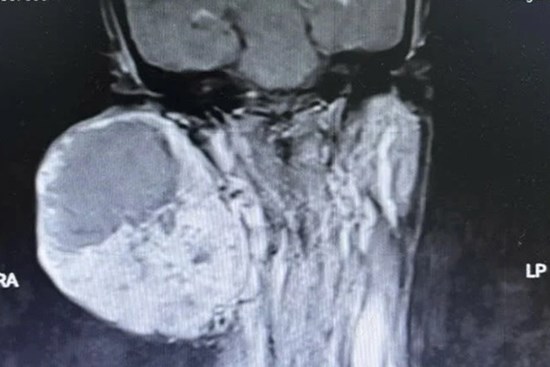

Cứu bệnh nhân bị 'nổ tung' khối u khổng lồ

Nam bệnh nhân nhập viện trong tình trạng khối u khổng lồ chiếm trọn vùng hàm dưới đè ngang cổ bị vỡ, máu tuôn ào ạt. Các bác sĩ đã nỗ lực cấp cứu, giữ lại sinh mạng người bệnh khi đã cận kề cửa tử.